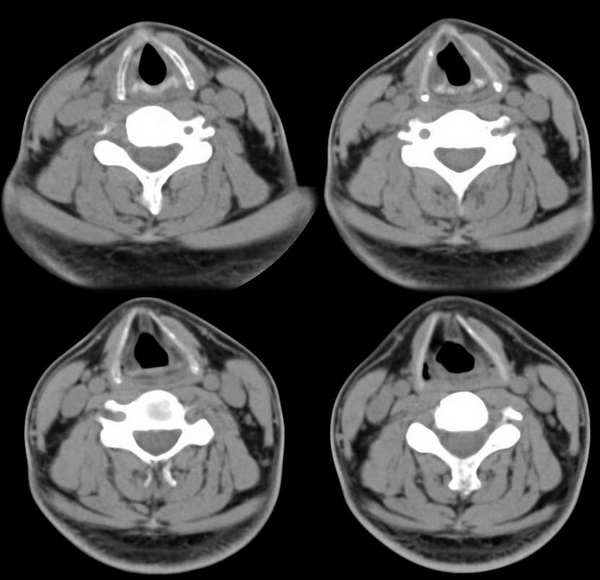

男,25岁,体温39.3度,发现右侧颈部包块.

右侧甲状腺内边界不甚清楚之占位,增强强化不很明显,无钙化。考虑腺瘤,建议活检,除外ca。

从片子上看考虑腺瘤可能性大,此病内有发热,急性炎症有除外。

考虑右侧甲状腺腺瘤.

会不会是甲状腺脓肿

肿块还是有强化的,会不会是甲状腺癌呢?但是体温39.3度不好解释,等待高手发言

支持脓肿!!!

左侧甲状腺肿大,增强时较对侧密度低。考滤炎症可能性为大。这种病灶要用影象检查时还算彩超较ct为好

考虑右甲状腺腺瘤可能大.

考虑右侧甲状腺腺瘤。

右侧甲状腺内边界不甚清楚之占位,增强后呈轻度强化。

1.考滤炎性病变可能性大;2.不除外ca。

临床怀疑甲状腺炎

平扫和增强病灶境界欠清、形状不规则,考虑甲状腺癌可能。

右侧甲状腺炎

此病例特点:1、年轻男性,基本上是高热;2、右侧甲状腺肿大呈边界不清之低密度,但甲状腺境界清晰;3、基本没有增强但低密度的周边略呈边缘增强反应;4、最好补充病史:痛否?时间?(如痛、急性起病。)

据此,以甲状腺急性炎症可能性大。

甲状腺脓肿